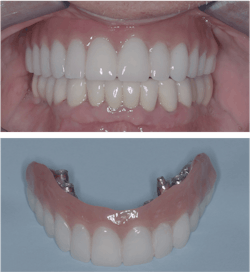

What should we do with them? The techniques now dominating almost all of dentistry are the final answers: tooth removal, complete fixed or removable dentures, implants, conservative “all-on-X” procedures (Locator fixed), periodontal surgery, bone grafting, endodontic treatment, and other complex treatments (figures 4 and 5).